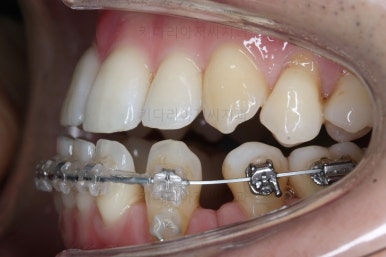

부산비수술교정 키다리아저씨치과에 처음 내원하셨을 당시의 입 안의 모습입니다.

아래 앞니에 결손치아가 하나 있네요. 송곳니-송곳니 사이에 앞니가 4개가 있어야 정상이지만 이 분은 3개에요. 의외로 아래앞니 하나 혹은 두개가 없는 경우가 굉장히 많답니다.

갯수가 맞지 않다보니 치열의 중앙도 맞지 않고 비대칭이 됩니다.

그리고 주걱턱이기 때문에 당연히 아랫니들도 앞으로 나올 수 밖에 없어 윗니보다 앞에 나와있어요.

이를 반대교합이라고 합니다.

장치를 처음 부착했을 때의 입안 모습입니다.

아랫니가 해야될 작업이 많고 기간이 오래 걸리기 때문에 윗니는 최대한 늦게 장치를 부착하여 불편감을 최소화 하기로 했어요.